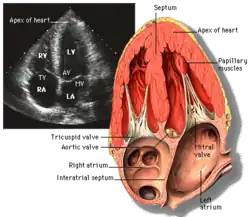

Apical four chamber (A4C)

This view is obtained at the apex of the heart and looking toward the base of the heart (where the valves are). In this view, the mitral valve, tricuspid valve, and all four chambers are visible. This view shows the right ventricle from base to apex and is a useful view to estimate RV systolic function. TAPSE (= tricuspid annular plane systolic excursion) is also measured in this view with M-mode through the lateral tricuspid annulus.

Structures:

- Inferior septum and anterior lateral segments of the left ventricle

- Right ventricle

- Left atrium

- Right atrium

- Mitral valve

- Tricuspid valve